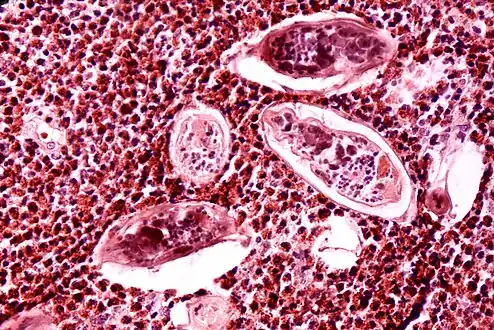

High-powered detailed micrograph of Schistosoma parasite eggs in human bladder tissue

Diagnosis of infection is confirmed by the identification of eggs in stools. Eggs of S. mansoni are about 140 by 60 µm in size and have a lateral spine. The diagnosis is improved through the use of the Kato technique, a semiquantitative stool examination technique. Other methods that can be used are enzyme-linked immunosorbent assay, circumoval precipitation test, and alkaline phosphatase immunoassay.[34]

Microscopic identification of eggs in stool or urine is the most practical method for diagnosis. Stool examination should be performed when infection with S. mansoni or S. japonicum is suspected, and urine examination should be performed if S. haematobium is suspected. Eggs can be present in the stool in infections with all Schistosoma species. The examination can be performed on a simple smear (1 to 2 mg of fecal material). Because eggs may be passed intermittently or in small numbers, their detection is enhanced by repeated examinations or concentration procedures, or both. In addition, for field surveys and investigational purposes, the egg output can be quantified by using the Kato-Katz technique (20 to 50 mg of fecal material) or the Ritchie technique. Eggs can be found in the urine in infections with S. haematobium (recommended time for collection: between noon and 3 PM) and with S. japonicum. Quantification is possible by using filtration through a nucleopore filter membrane of a standard volume of urine followed by egg counts on the membrane. Tissue biopsy (rectal biopsy for all species and biopsy of the bladder for S. haematobium) may demonstrate eggs when stool or urine examinations are negative.[35]